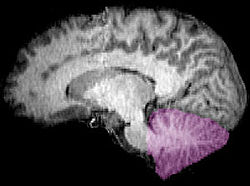

Figure 1b: MRI image showing a mid- sagittal view of the human brain, with the cerebellum in purple.

The cerebellum is located in the inferior posterior portion of the head (the hindbrain), directly dorsal to the pons, and inferior to the occipital lobe (Figs. 1 and 3). Because of its large number of tiny granule cells, the cerebellum contains more than 50% of all neurons in the brain, but it only takes up 10% of total brain volume. The cerebellum receives nearly 200 million input fibers; in contrast, the optic nerve is composed of a mere one million fibers.